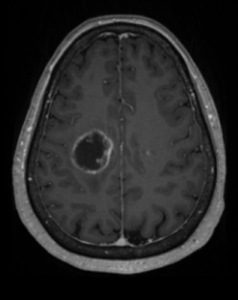

HALLAZGOS RADIOLÓGICOS